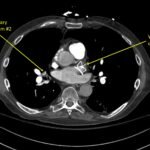

A 78-year-old gentleman presented to the emergency department (ED) for palpitations and dizziness. He had a complicated medical history including atrial fibrillation (AF), recently status post a Watchman procedure, oxygen-dependent chronic obstructive pulmonary disease (COPD), and heart failure with preserved ejection fraction (HFpEF). Point-of-care ultrasound (POCUS) revealed the presence of an intracardiac right atrial thrombus. Computed tomography (CT) angiography confirmed the presence of multiple pulmonary emboli (PE), and extension of the thrombus into the inferior vena cava. Pulmonary emboli are a common complication of thrombus in the right atrium. Management may include anticoagulation, thrombolysis, or thrombectomy. This case highlights that emergency physicians can expedite the diagnosis of intracardiac thrombus by using POCUS. The case presented describes a medically complex patient presenting with symptomatic right intracardiac and inferior vena caval thrombosis complicated by multiple PE. Point-of care ultrasound of the heart and lungs were included in his initial assessment, revealing findings of an intracardiac thrombus, and ruling out multiple other differential diagnoses including pericardial tamponade, pleural effusion, pulmonary edema, and pneumothorax. This finding changed the trajectory of this patient’s evaluation and management, and demonstrates the important role of POCUS in the care of ED patients with undifferentiated cardiopulmonary symptoms.